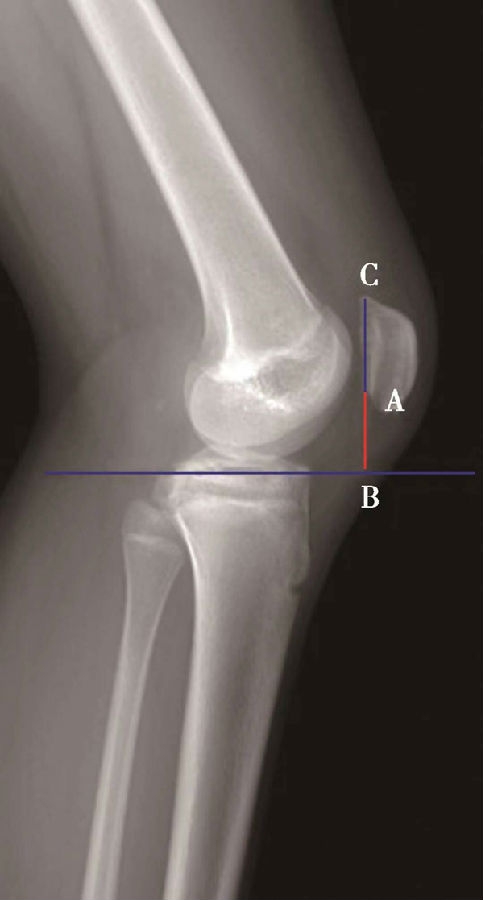

如图示:AB为髌骨关节面最低点到胫骨平台轮廓前上角最短的距离,AC是髌骨关节面的长度。Caton指数=AB/AC(图1)。

图1

图2 Caton指数=AB/AC=1.10,为正常髌骨高度

临床工作中常常使用其来估计胫骨结节移位的效果。正常人的Caton指数=1,正常范围0.8~1.2(图2)。需要注意的是:术前规划胫骨结节需要移位的理论距离为AB-AC,这就是需要将胫骨结节向远端移位的最大距离。但在术中胫骨结节转移的距离往往要小于这个距离,避免因过度移位造成医源性的低位髌骨。